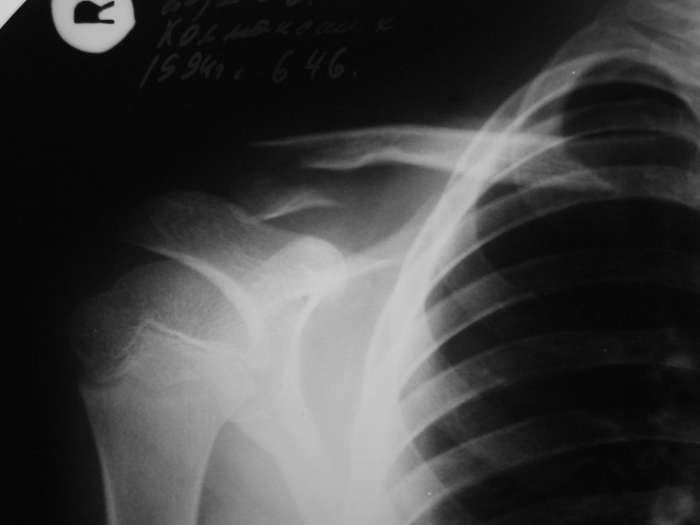

НЗ> 2. Нет ли на снимке перелома хирургической шейки плеча? Сам

Нет.

Александр, простите за настойчивость, на картинке я указал смутившую меня тень ... это вариант зоны роста?

> смутившую меня тень ... это вариант зоны роста?

Это контур зона роста на передней поверхности кости.

Перелома плеча нет, это зона роста с другой стороны кости.

По поводу проксимального плеча, согласен с вами, перелома нет - видна линия ростковой зоны.